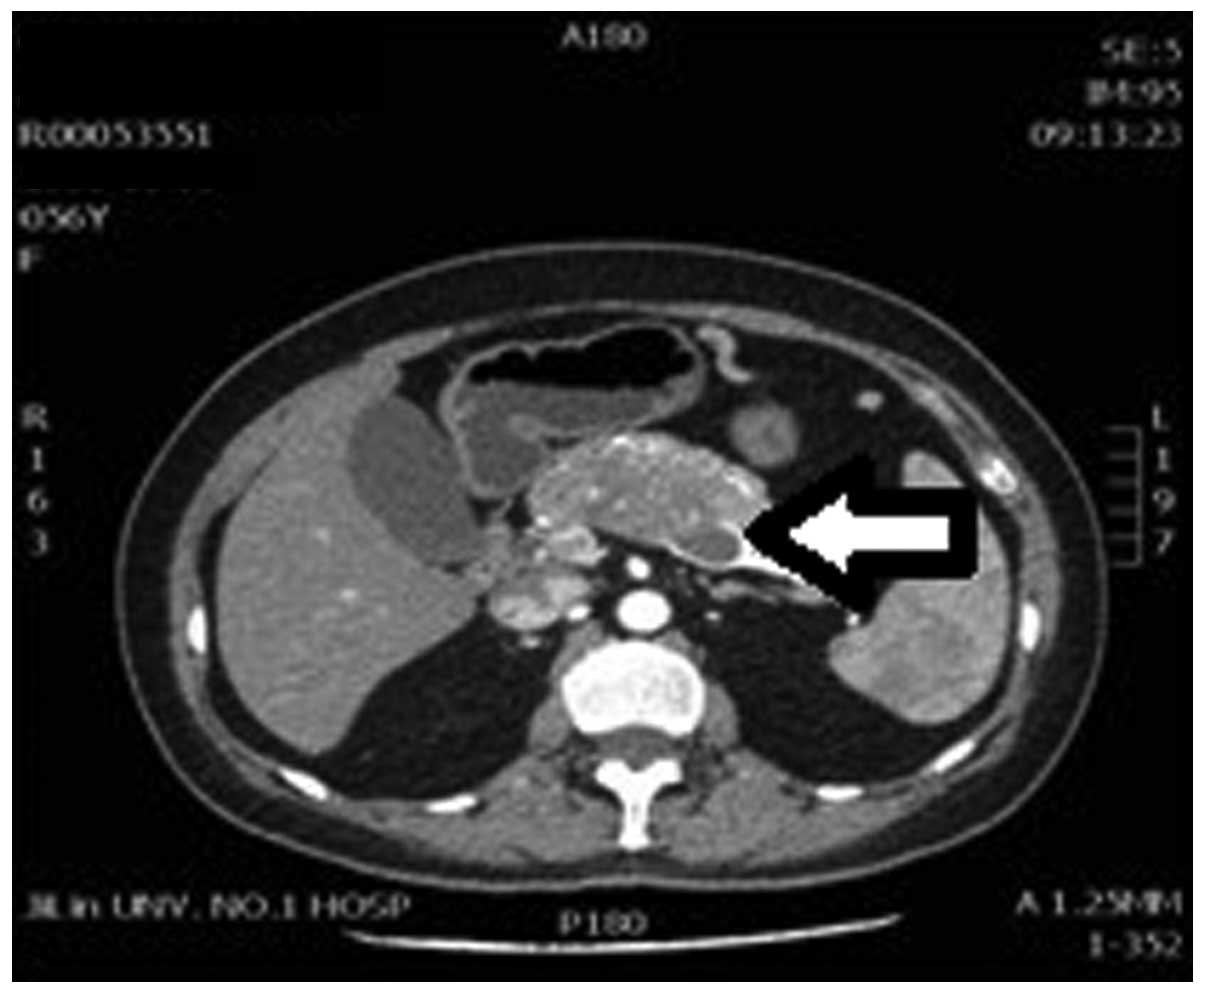

Contrast Enhanced Ct Scan The Arrow Points At A Well Encapsulated Download Scientific Diagram

www.researchgate.net